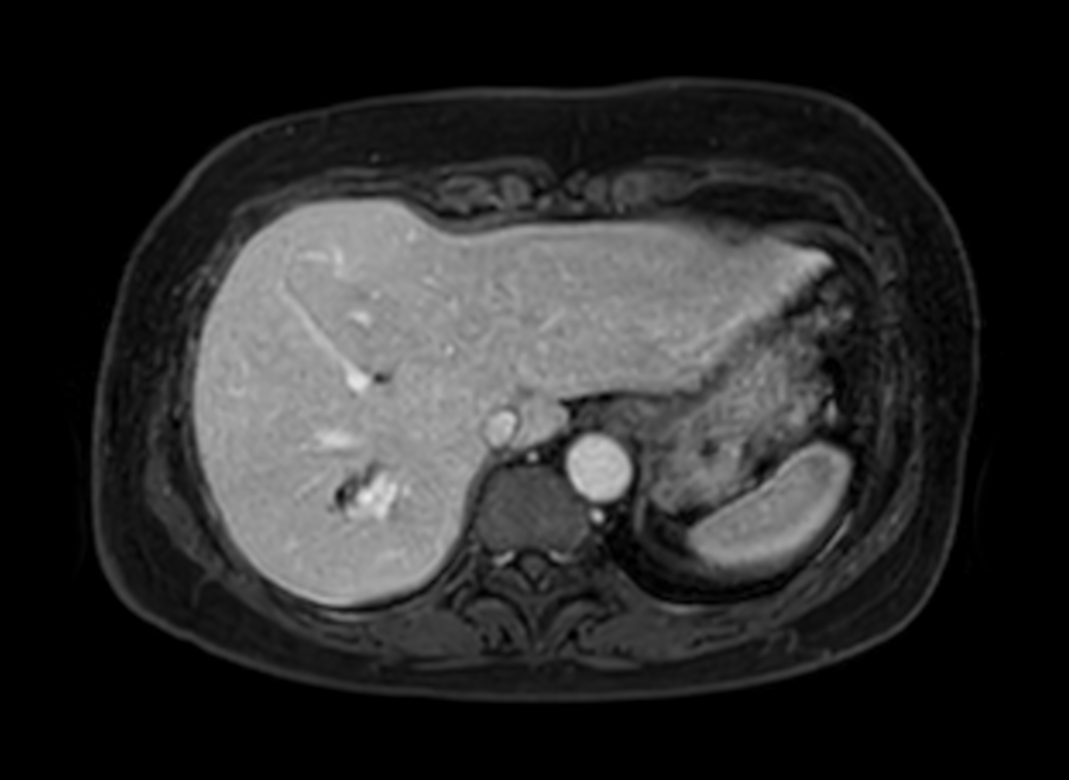

Axial eTHRIVE (1st dynamic)

Axial eTHRIVE (2nd dynamic)

Axial eTHRIVE (4th dynamic)